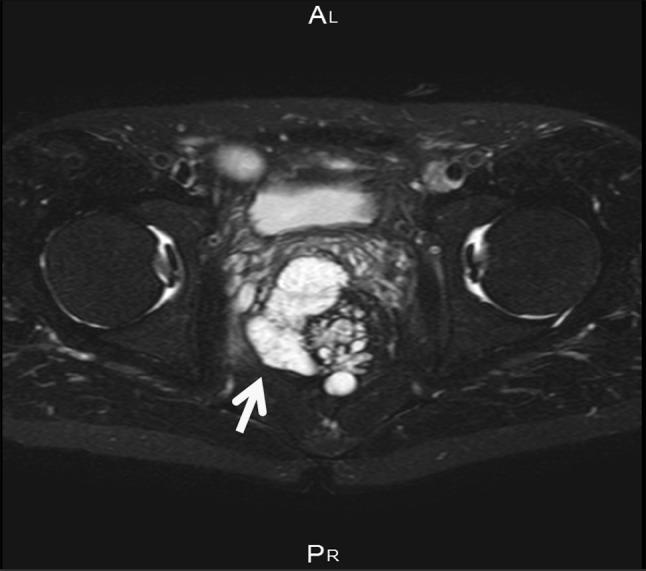

We analyzed 34 patients (26 men, 8 women, median age at cancer diagnosis 43.5 years, duration of illness 18 years) and found that the number of those with CD complicated with cancer began to drastically increase after 2005. The site of onset of cancer was in an anorectal lesion in 24 (70.6 %) patients. In 17 (50 %) patients, the cancer was diagnosed before surgery; in 3 patients (8.8 %), it was based on pathological findings during surgery; and in 14 patients (41.2 %), it was based on postoperative pathological findings. Mucinous carcinoma was the dominant histological type, seen in 15 patients (44.1 %), while the special type of signet-ring cell carcinoma was found in 4 patients. The cumulative overall 5 year survival rate was 46.2 %.

我们分析了34例患者(男性26例,女性8例,癌症诊断时的中位年龄为43.5岁,病程18年),发现2005年后CD合并癌症的患者数量开始急剧增加。癌症的发病部位在24例(70.6%)患者中为肛肠病变。17例(50%)患者在手术前被诊断出癌症;3例(8.8%)基于手术中的病理发现;14例(41.2%)基于术后病理发现。黏液癌是主要的组织学类型,见于15例患者(44.1%),而特殊类型的印戒细胞癌见于4例患者。累计5年总生存率为46.2%。